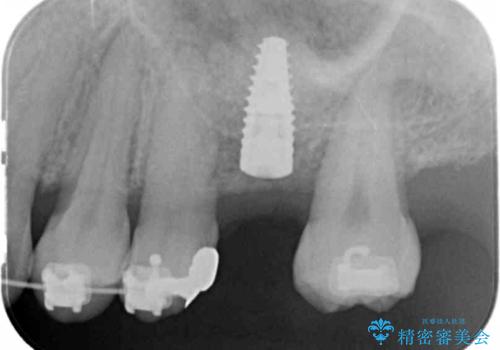

最終的な歯の位置を矯正の担当医と綿密に相談しながら、インプラントの埋入部位を決定し治療にあたりました。

骨量が少なかったことから、上顎洞内へのソケットリフト方をインプラント埋入と同時に施行しています。

- 51.4万円(ストローマンインプラント・ソケットリフト・仮歯・カスタムアバットメント・ジルコニアクラウン)費用は治療当時の料金となります